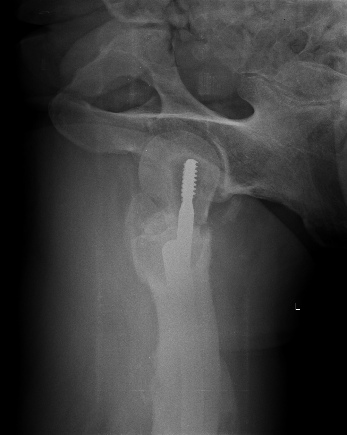

Винт был введен недостаточно глубоко, и главное - длина бедра не была полностью восстановлена.

Реостеосинтез проксимальным гвоздем тут проблематичен, надо исхитриться сделать то, что не сделали при первичном остеосинтезе, т.е. вальгусную репозицию, восстановить длину бедра, и винт ввести не в имеющийся канал, а кпереди, и буквально субхондрально.

Здесь надо хорошо вальгизировать проксимальный отдел, поскольку диафиз смещен проксимально - вот так бы неплохо сделать, как на картинке. И 130 градусная пластина подойдет для этого гораздо лучше, 95 градусную тут вряд ли для такой коррекции можно разместить.